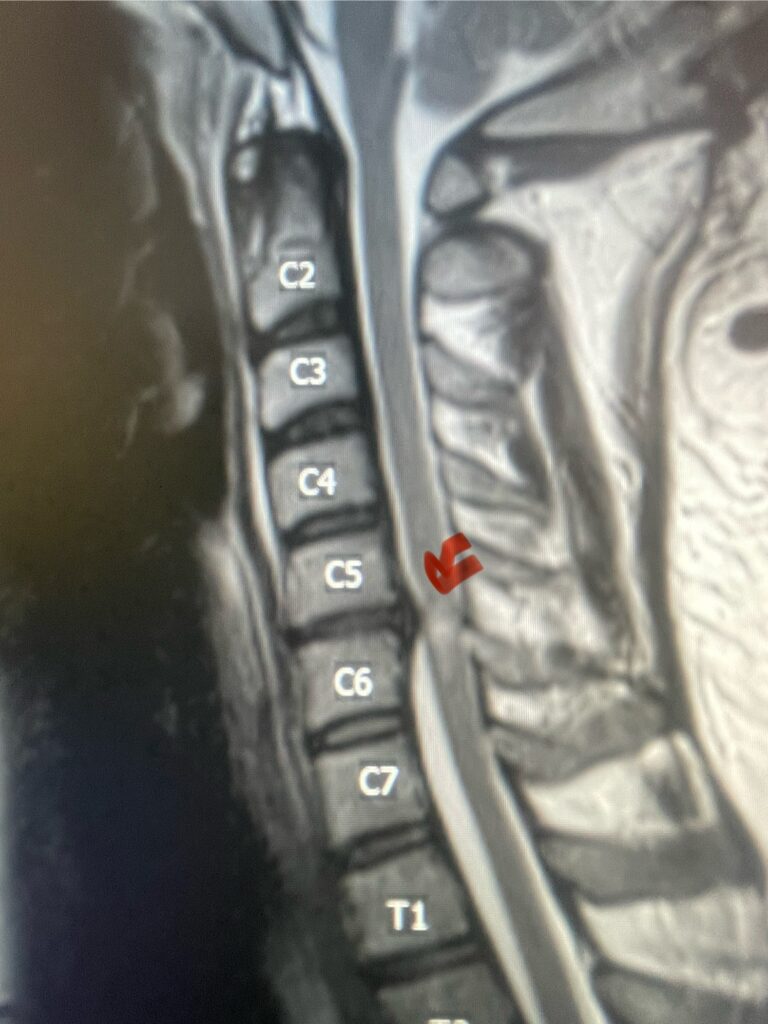

Here is a tough case: This is a 72 year-old male who presented with several months of progressive neck pain without symptoms of the arms or legs. […]